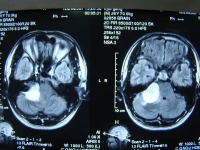

听神经瘤早期出现眩晕应与内耳眩晕前庭神经元炎迷路炎及各种药物性前庭神经损害相鉴别前者有进行性耳聋并伴面神经功能障碍 .耳聋应与内耳硬化症药物性耳聋相鉴别听神经瘤都有前庭神经功能障碍 .与脑桥小脑角其他肿瘤相鉴别:①上皮样囊肿:首发症状多为叉神经根刺激症状听力下降多不明显前庭功能多属正常CT, MRI可协助鉴别②脑膜瘤耳鸣与听力下降不明显内耳道不扩大③脑干或小脑半球胶质瘤:病程短脑干或小脑症状出现的较早早期出现锥体束征④转移瘤起病急病程短其他部位可能找到原发癌。

星形细胞瘤:第脑室上方的星形细胞瘤常表现为鞍上实性肿块般不伸延到鞍内钙化率较颅咽管瘤低但与鞍上实质型的颅咽管瘤有时较难给别 ②脑膜瘤:脑膜瘤有%发生在鞍上平扫呈均匀稍高密度可有钙化囊变少见肿瘤常位鞍上偏前的位置鞍结节骨质增生垂体瘤:可突向鞍上常引起蝶鞍扩大鞍底下陷海绵窦受累且因出血坏死发生囊性变但钙化罕见 ④动脉瘤:巨大动脉瘤壁上可有钙化增强扫描时瘤壁因有机化组织而强化但动脉瘤腔内有血液的地方强化非常显著与颅内动脉强化致偶尔强化均匀的动脉与实质型的颅咽管瘤鉴别较为困难要仔细分析瘤体与大脑动脉环诸血管的关系不能区分时要行MR检查或脑血管造影